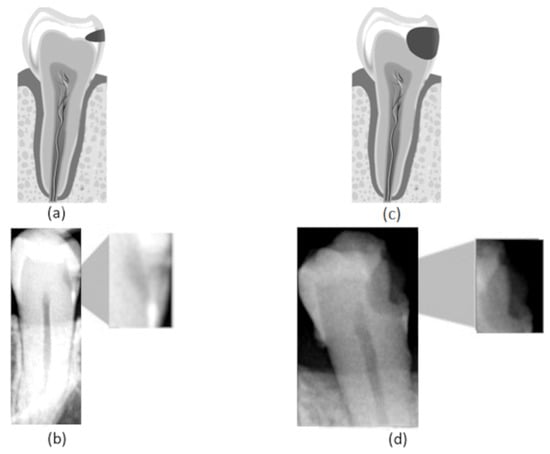

Figure 1.

(a) Representation of an incipient caries lesion, (b) bitewing image with incipient lesion highlighted, (c) representation of an advanced caries lesion, (d) bitewing image with advanced lesion highlighted.

In this work, we consider three different caries stages based on their lesion severity: normal, incipient, and advanced. The normal class consists of teeth with no lesion. The incipient class denotes teeth with superficial lesions affecting the enamel—Figure 1a,b. Finally, the advanced class refers to teeth with advanced lesions, affecting a considerable part of the tooth, expanding into the dentin and the pulp—Figure 1c,d.